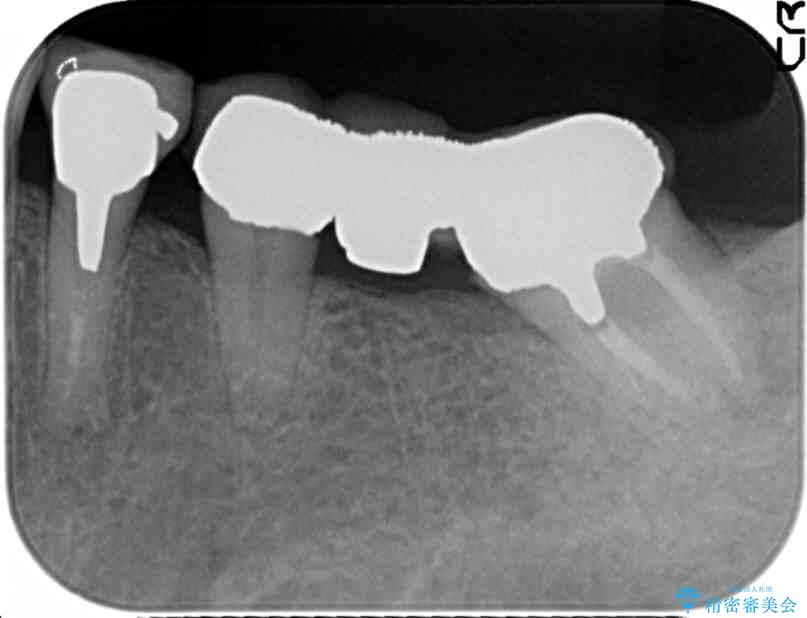

治療前

劣化の進んだブリッジの再治療[ 不適合な補綴物による虫歯の再発 ] 治療前画像 劣化の進んだブリッジの再治療[ 不適合な補綴物による虫歯の再発 ] 治療前画像 劣化の進んだブリッジの再治療[ 不適合な補綴物による虫歯の再発 ] 治療前画像